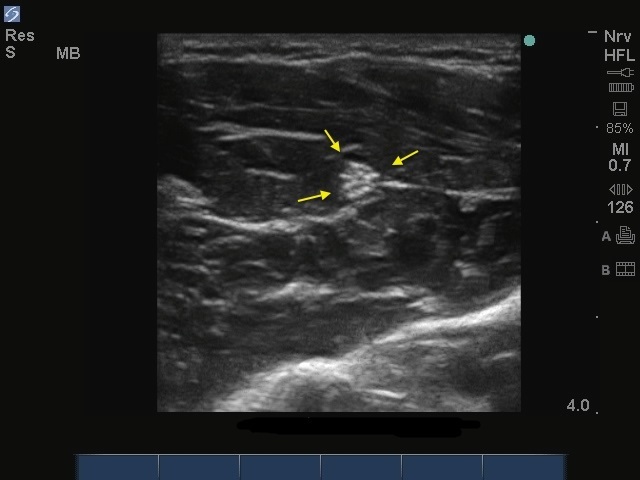

S-System : Image, nerf musculocutané

Flèches : nerf musculocutané